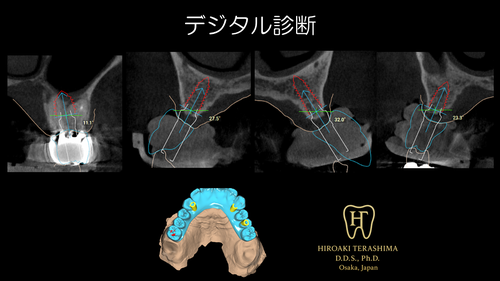

✔ デジタルシミュレーションによる安全性向上

✔ サージカルガイド使用